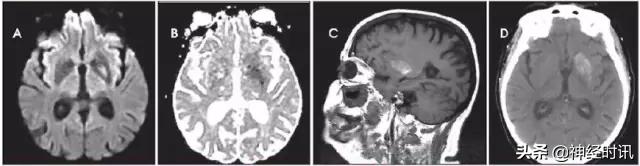

图9 一例53岁女性,酒精性肝硬化,因腹痛、恶心和呕血就诊于急诊。数天后,她出现无反应,伴脑干反射消失,血*水氨**平达360。她被诊断为肝性脑病,MRI显示双侧额叶和岛叶皮层和丘脑轻度弥散受限(A:DWI,B:ADC)和FLAIR高信号(C)。豆状核有轻度T1高信号(D)。

克雅氏病